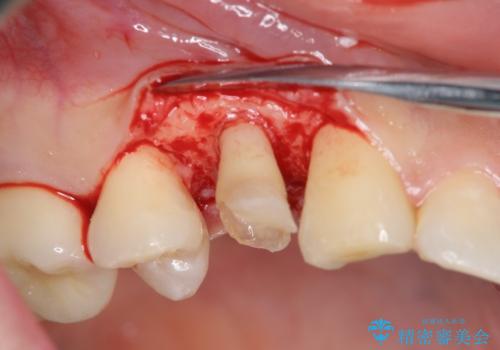

虫歯を取り切った後は、歯を引きあげたことで一緒に上がってきてしまった骨をならしていきます。

その後ラバーダムをして根っこの治療をし、被せ物を被せて治療終了となりました。